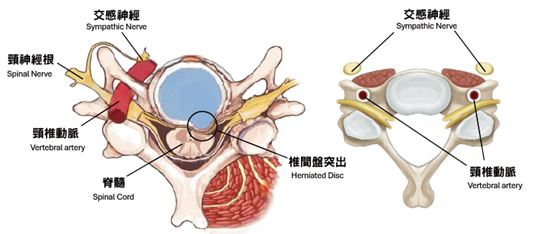

「頸源性頭暈」便是指疾病是與頸部問題最為相關。頸是連接頭部與軀幹的橋樑,它包含脊椎、血管 和神經組織(Fig.1),對活動和生存至關重要,任何傷害這條橋樑或這條橋樑出現病患,對維持人體健康或身體機能有關鍵影響,例如: 出現長期的頭暈頭痛。

頸椎結構圖:

主要頸源性頭暈、頭痛的成因: (1)上頸椎神經受壓:

因為頸椎分為上頸椎和下頸椎,頸椎C3節為分介線,C3以上椎節為上頸椎節,C3以下椎節為下頸椎節。凡是上頸椎神經受壓,例如:椎間盤突出、椎孔狹窄、椎體移位或下陷,都會有機會導致前額痛、後枕痛、眼窩痛、上頸椎痛。

(2)刺激交感神經:

抬頭或擺動頭部或頸椎,轉移體位刺激到交感神經,使頭暈、頭痛、眼花、心跳等症狀更加明顯。

(3)頸椎內外血管扭曲:

抬頭、擺動頭頸部或長期姿勢不良等,導致頸椎內外血管流動不暢順,影響血液來往腦區域,導致頭暈、頭痛。